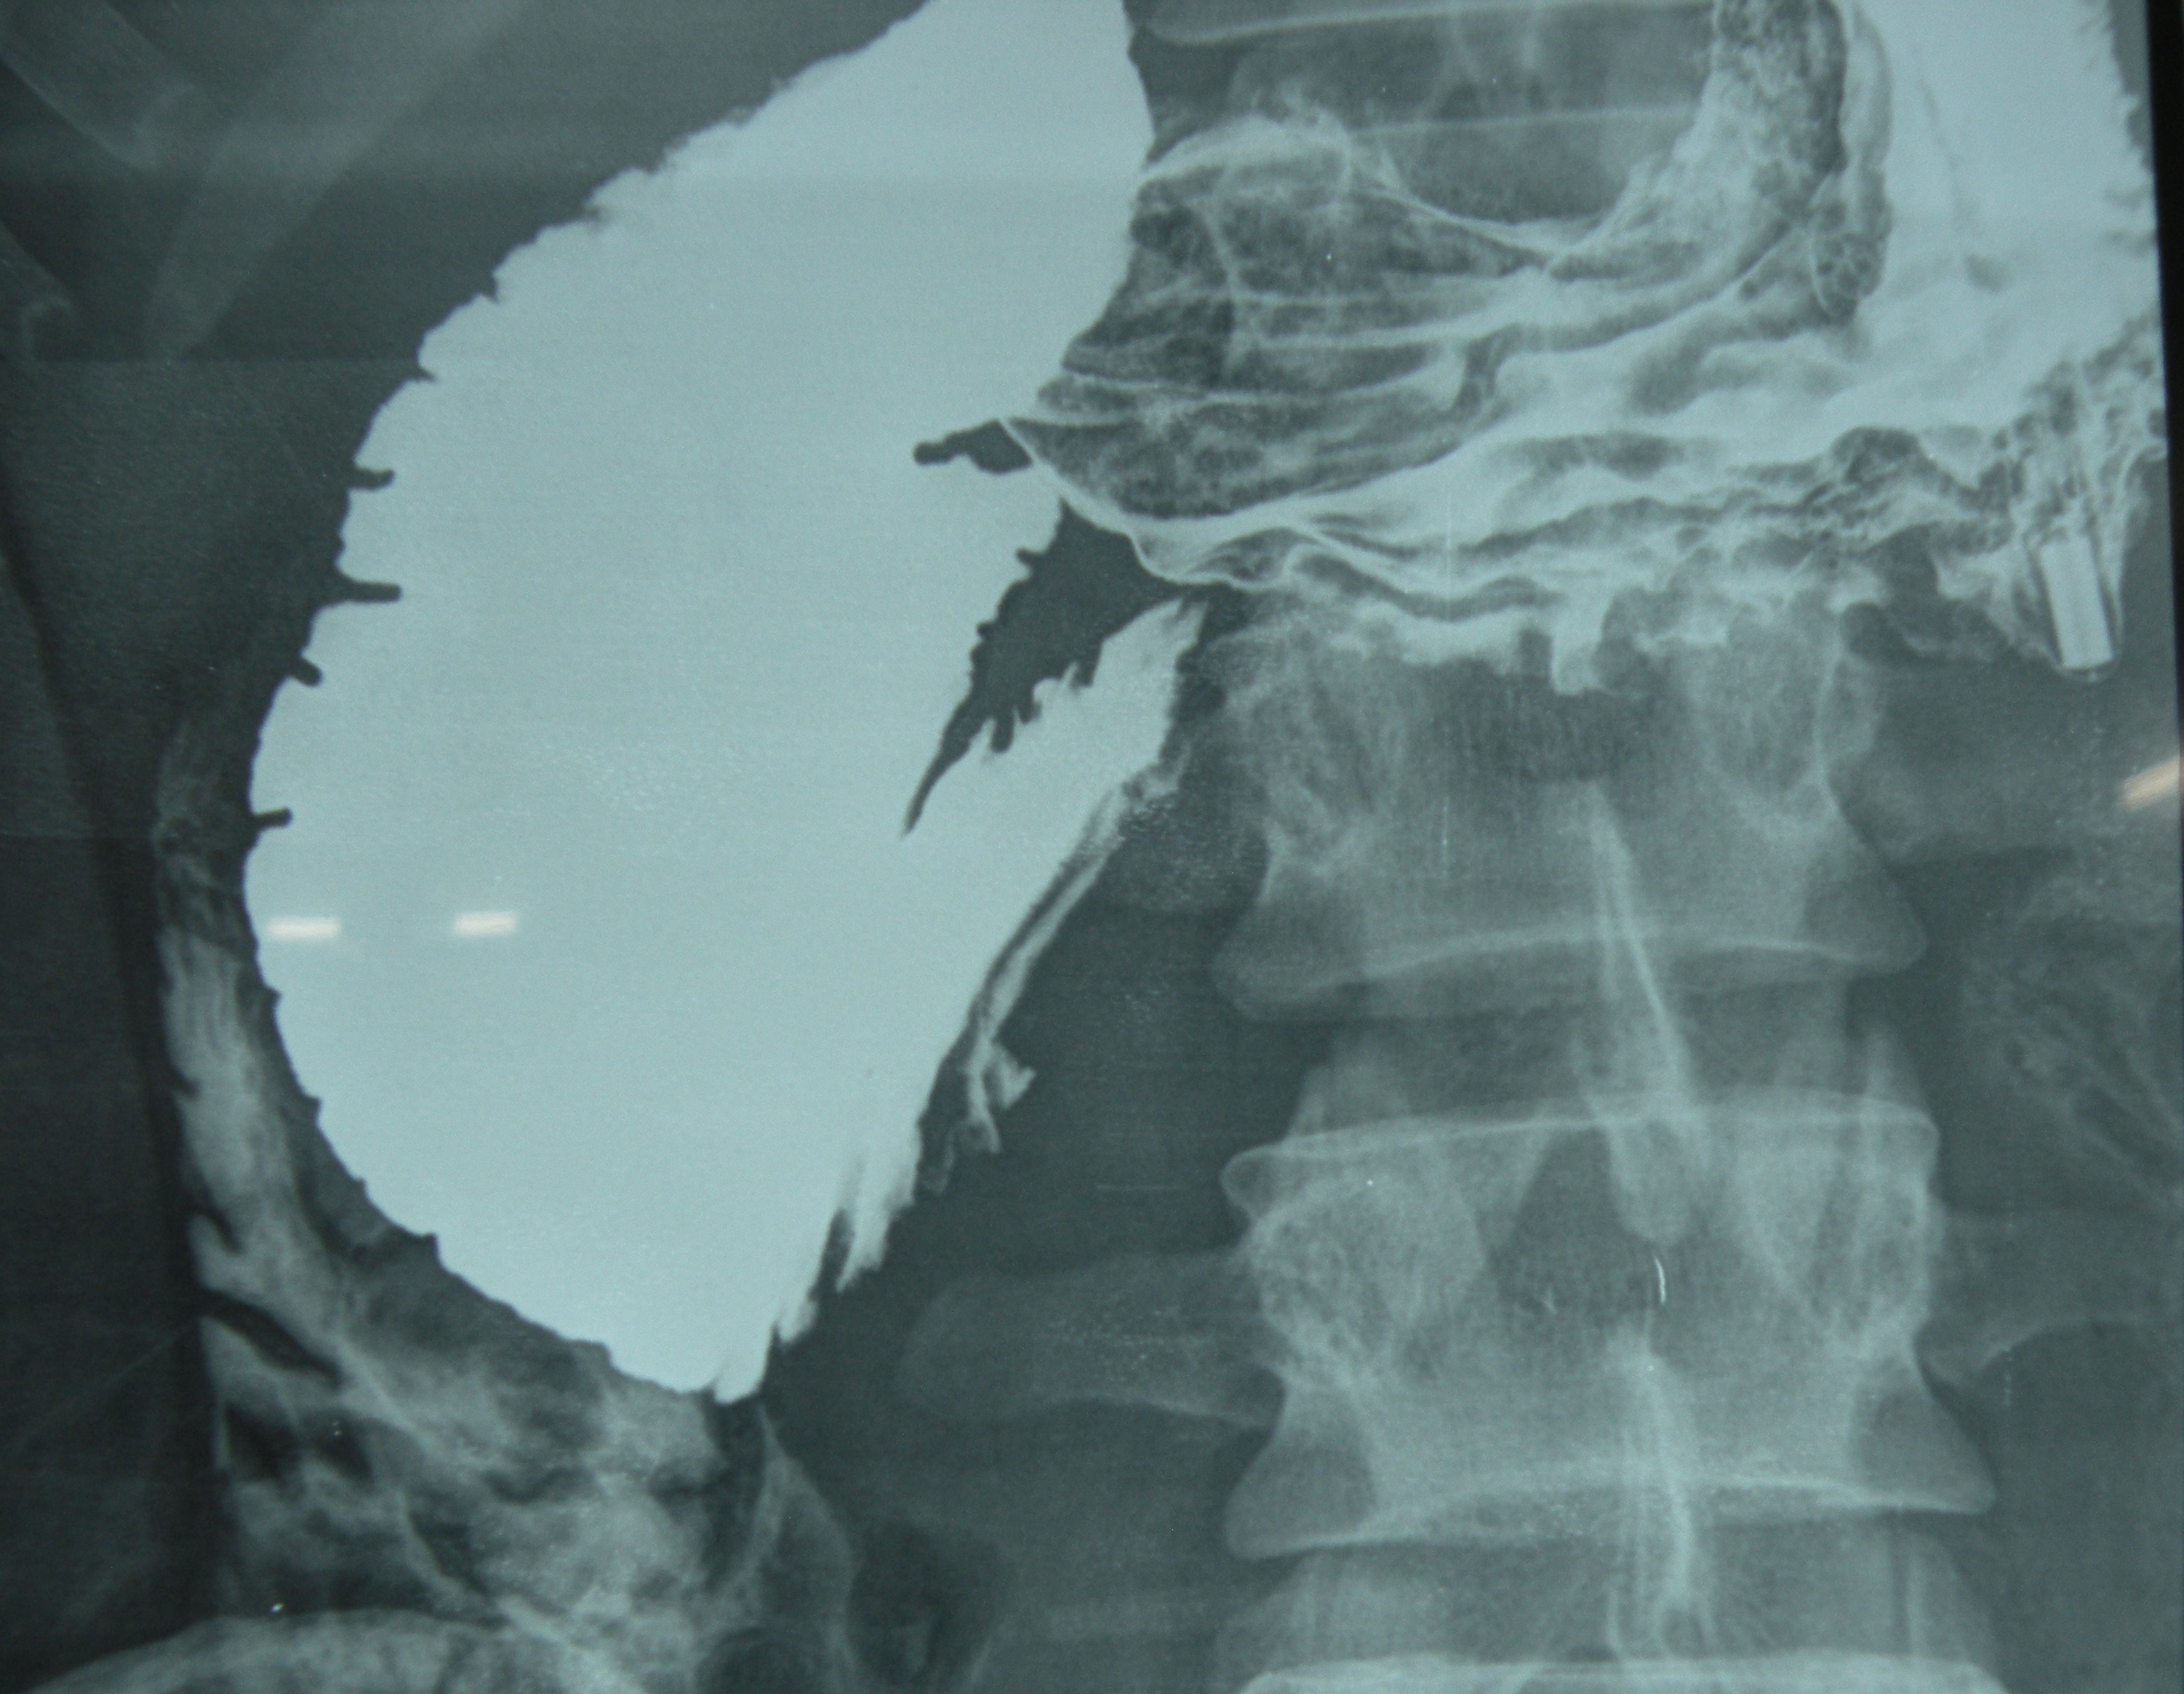

Roux-en-Y duodenojenunostomy for SMA syndrome. The young patient (27 years old) had undergone an appendicectomy (perhaps a wrong diagnosis) at Samana about two weeks back, but continued to have abdominal pain and vomiting. Barium study revealed a dilated duodenum up to the third part.

The angle between the aorta and SMA was 15 degrees on CT angiography.